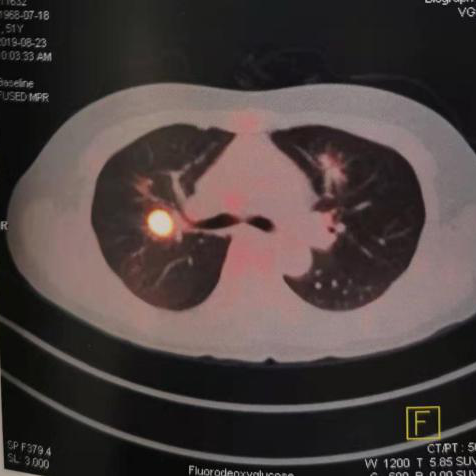

2019年8月(51岁),来院检测CT示肺部阴影,PET-CT示高代谢病灶。行超声支纤镜活检示:低分化鳞癌。

图2:2019年8月23日CT及PET-CT结果

PET-CT: 2019/8/23

(靶向治疗前)